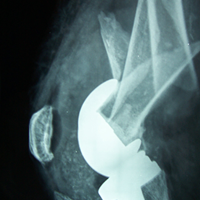

Case:7 Fracture Neck Femur with Implant failure and Re-Fixation with hemi-arthroplasty

Alcoholic Gardener by profession had slipped in bathroom & fell. He sustained fracture neck femur.He was operated with closed reduction & CC Screw fixation under IITV. Two weeks’ post fixation he again fell & sustained fracture in sub trochanteric region. He was treated with Hem-Arthroplasty with Tension band wiring.

Pre-Op

Post-Op

Post Fall

Oblique-Post Fall

Lat-Post Fall

Lateral-Post Prosthesis Fall

Post Prosthesis Fall

Post Uninon-3Months